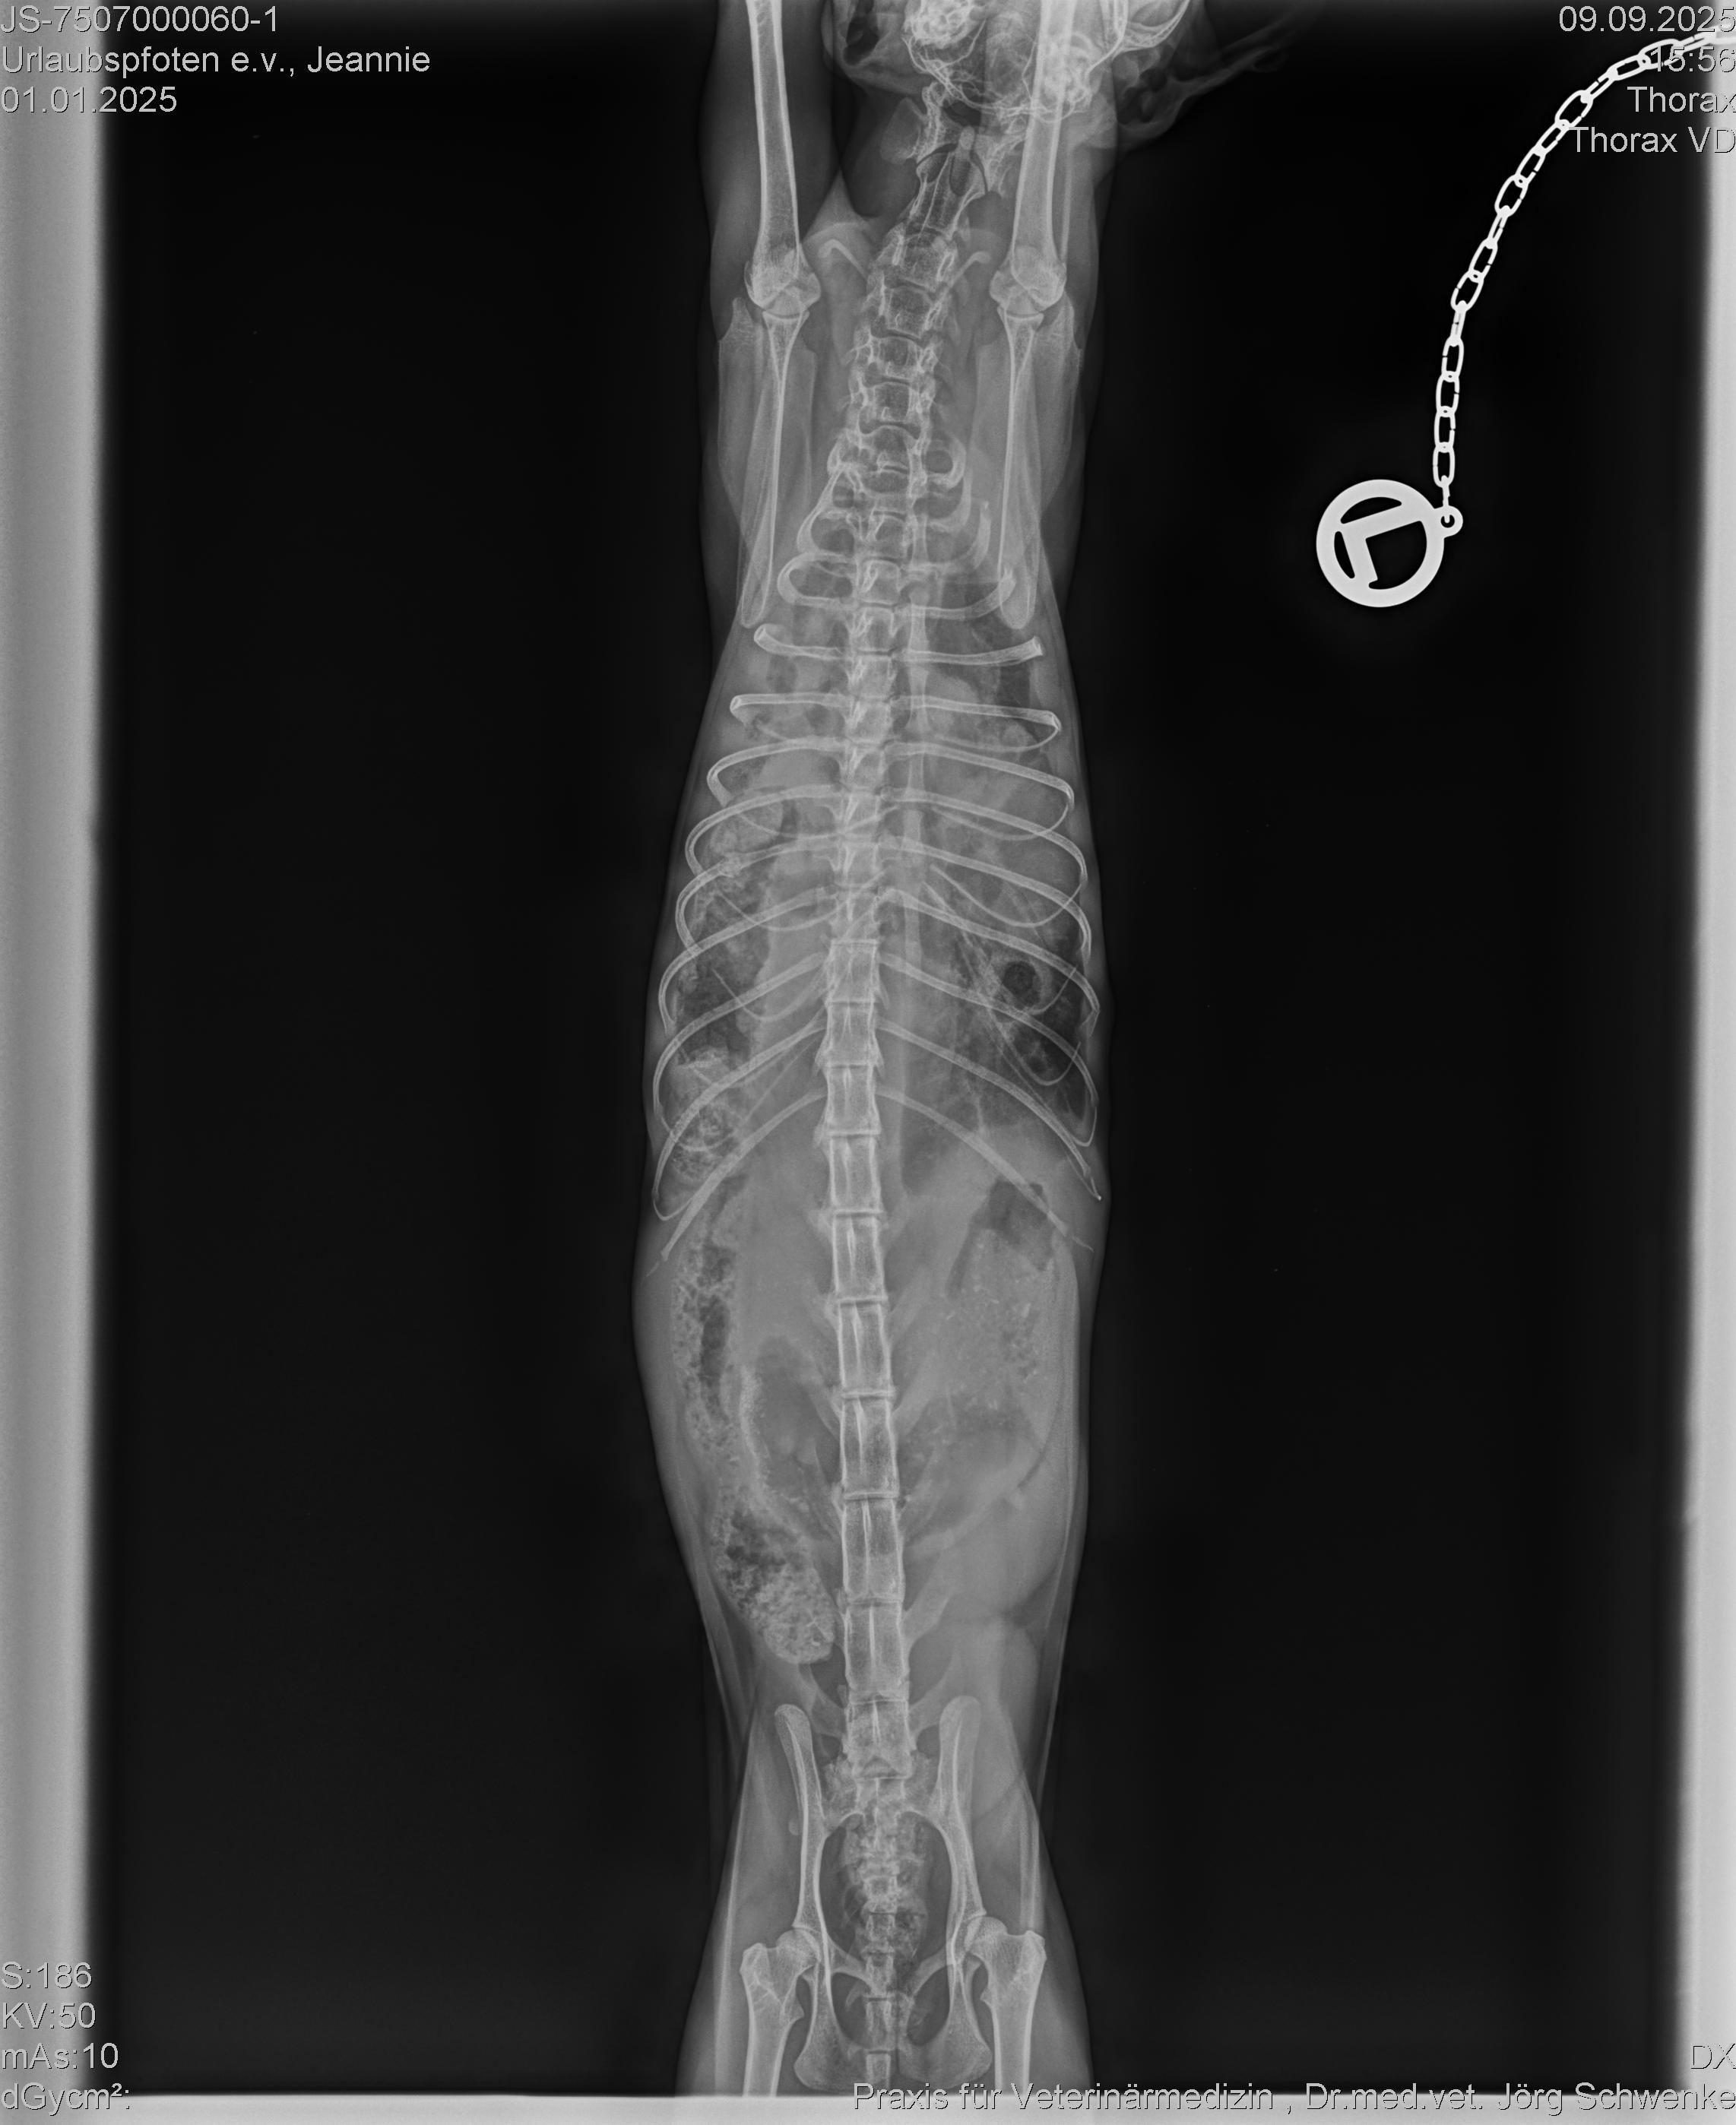

Jeannie, eine knapp einjährige Mutterkatze, hat eine Zwerchfellhernie, die dringend operiert werden muss. Was ist eine Zwerchfellhernie? Das ist ein Zustand, bei dem sich der Magen oder andere Bauchorgane durch eine Lücke oder einen Defekt im Zwerchfell in den Brustkorb verlagern. Sie bekommt ganz schlecht Luft, ist immer erschöpft und kann nur winzige Menge Futter zu sich nehmen. Wir, der Verein Urlaubspfoten e.V., haben Jeannie und ihre beiden Kitten Chip und Chap an einem Futterplatz sichern können. Dazu war wochenlange Vertrauensarbeit notwendig, bis die Kleinen gross genug waren und Jeannie sie nicht mehr verstecken konnte. Trotz ihrer schweren Beeinträchtigung hat es diese bezaubernde Katze irgendwie geschafft ihre Babies auf die Welt zu bringen, zu säugen und zu versorgen. Sie selbst blieb dabei fast auf der Strecke und ohne diese lebensnotwendige OP hat sie keine lange Lebenserwartung. Wir wollen ihr diese Chance gerne ermöglichen, brauchen dazu aber EURE HILFE!